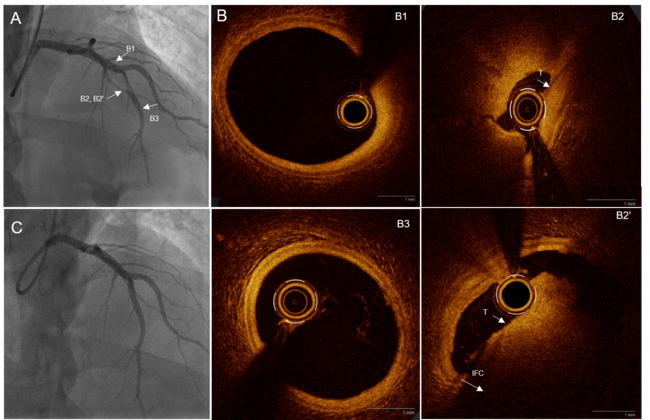

A 28-year-old man with no cardiovascular risk factors presented with an acute anterior ST-elevation myocardial infarction at H+6 after strenuous physical exertion (lifting an extremely heavy load). Emergent angiography revealed a 99% subocclusive stenosis of the mid-left anterior descending (LAD) artery involving a major bifurcation. While distal LAD Thrombolysis in Myocardial Infarction flow was severely impaired, flow in the large diagonal branch remained preserved (Figure A, Video 1).

Optical coherence tomography (OCT) was performed to identify the underlying mechanism. The procedure (crossing the lesion and contrast injections) was associated with mechanical reperfusion. The morphological assessment confirmed an intact fibrous cap diagnostic of plaque erosion. Comparison with the initial luminal narrowing (minimal lumen area [MLA] 0.9 mm²) demonstrated a significant mechanical luminal gain, with a post-reperfusion MLA of 2.6 mm² (Video 2). Precise measurements using the external elastic membrane identified a proximal LAD diameter of 4.4 mm and a distal diameter of 3.4 mm (Figure B).

Given the complexity of the bifurcation and the favorable anatomical result after mechanical reperfusion, a stentless strategy was adopted. Management was exclusively pharmacological, maintained with dual antiplatelet therapy (aspirin 75 mg QD and ticagrelor 90 mg BID) and full anticoagulation with enoxaparin for 8 days. Notably, no glycoprotein IIb/IIIa inhibitors were used. Extensive thrombophilia workup was negative. Follow-up angiography at day 8 showed complete resolution of the thrombus and a strictly normal angiographic appearance (Figure C, Video 3).